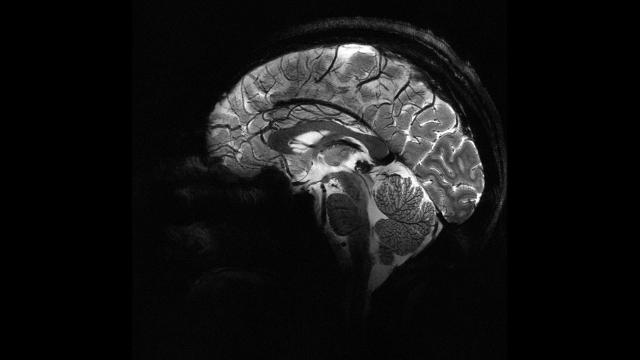

7NEWS.az xəbər verir ki, avstraliyalı tədqiqatçılar həkimlərin tez-tez gözdən qaçırdığı epilepsiya xəstəsi uşaqlarda kiçik beyin qüsurlarını aşkar edə bilən süni intellekt aləti hazırlayıblar. Mütəxəssislər deyirlər ki, bu sistem uşaqlara həyatını dəyişən cərrahi prosedurlara daha tez daxil olmaq imkanı verə bilər.